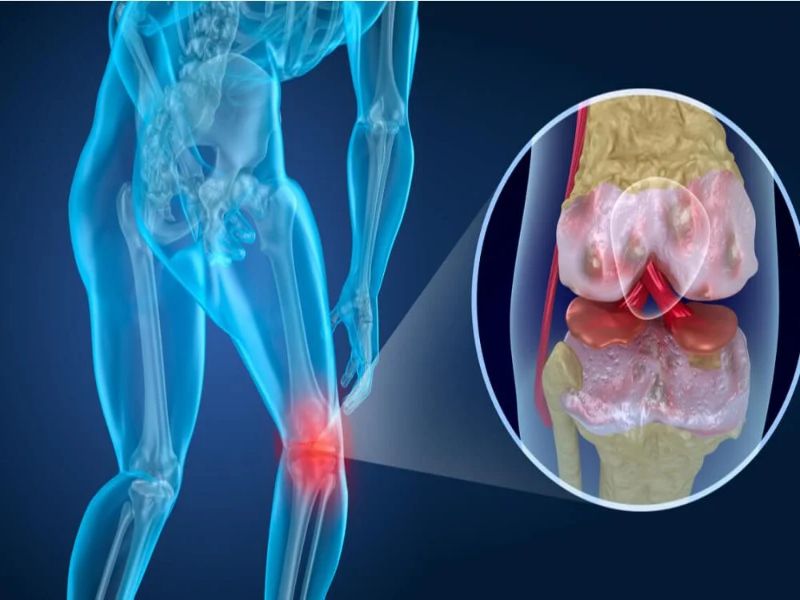

- Artrosis de rodilla

Las articulaciones de las rodillas la conforman el fémur, la tibia y el peroné. Este tipo de artrosis se caracteriza por el deterioro que genera el cartílago, provocando que se genere dolor con la actividad física, problemas para caminar y permanecer de pie. Esta enfermedad aparece en las personas antes de los 50 años de edad.